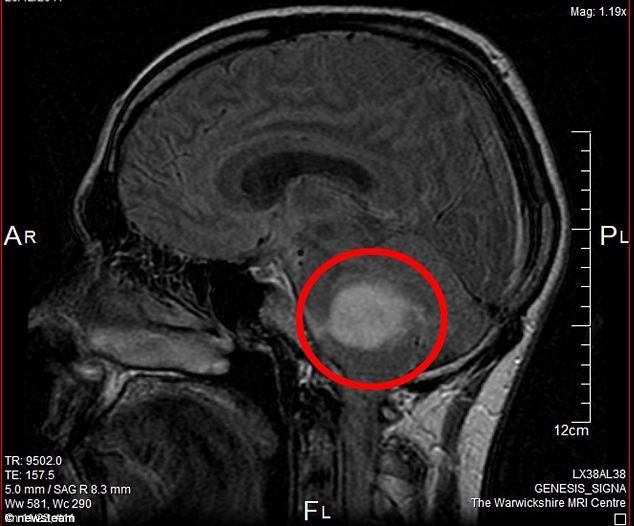

MRI (자기공명영상, MRI) Useful for soft tissue evaluation. (연부 조직(근육, 신경 등) 평가에 유용.)

• Applied in cases like brain tumors, laryngeal cancer.

(뇌종양, 후두암 등의 치료에 사용.)